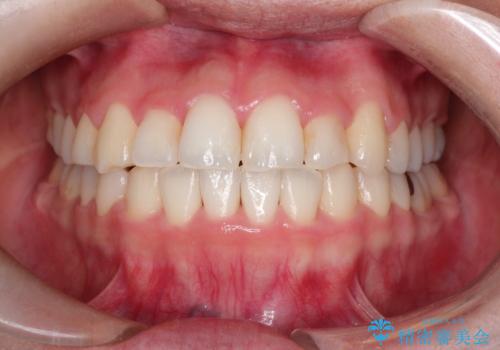

【インビザライン】前歯のねじれを治したい。

- 前歯の凸凹を主訴に来院されました。

スペースを作るために顎間ゴムを使用して、奥歯の遠心移動をおこない配列しました。

奥歯の遠心移動を行うことで、犬歯関係も良い状態に仕上げることができました。